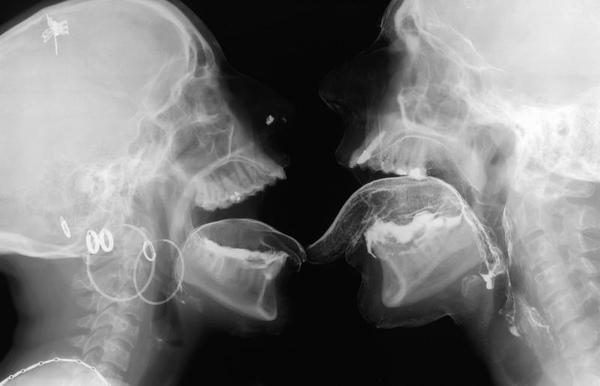

當愛愛的時候照X光...

喇舌還是輕口味的

重口味的在下面......